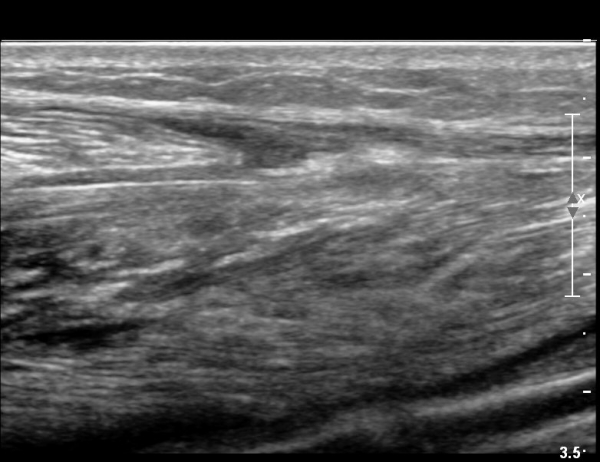

2018³â  1¿ù 30ÀÏ ÃßÀû°Ë»ç

¾ÆÅ³·¹½º°Ç Àú¿¡ÄÚºÎÁ¾ÀÌ °¨¼ÒµÇ°í  ÆÄ¿­ºÎÀ§ Àú¿¡ÄÚ°¡ È£ÀüµÇ¾î

°ÇÀÇ ¼¶À¯¼º¾ç»ó(fibrillar pattern)ÀÌ È¸º¹µÇ°í ±¹¼ÒÀû ¿¬°á¼º ¼Ò½ÇÀÌ »ç¶óÁü(»çÁø 9, 10, 11, 12).